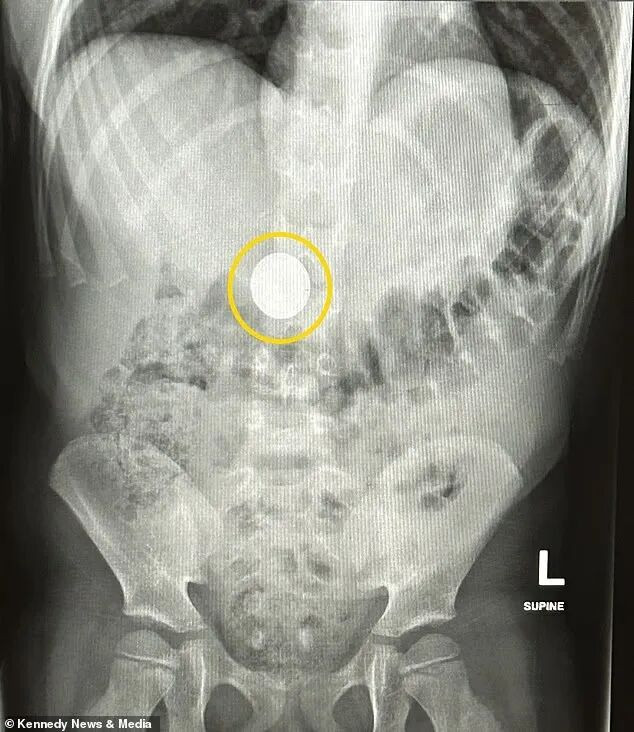

小女儿Lily告诉父母她吞下的是一枚硬币,但医院的X光检查却揭示她吞下的是一颗小小的扣式电池,来自其中一款跟踪器。

幸运的是,小Lily吞下的电池并未停留在食道中,避免了致命的化学灼伤。X光显示,电池已经进入她的肠道,虽然这依然是一个危险的状态。